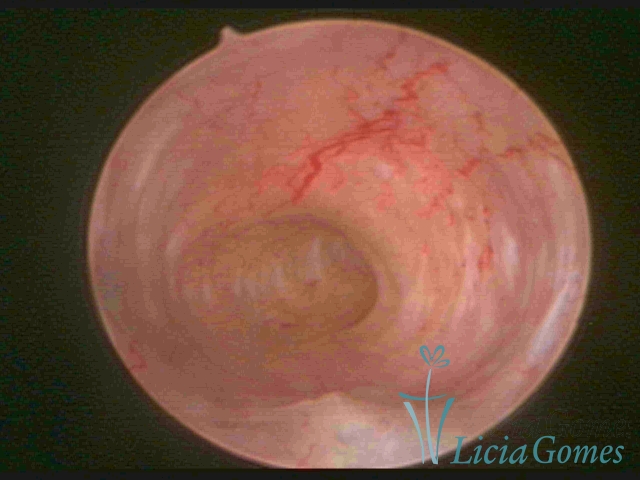

Uterus didelphys

The presence of two uterine cervices and a double vagina, similar to unicornuate uteri, with a normal covering of endometrium.